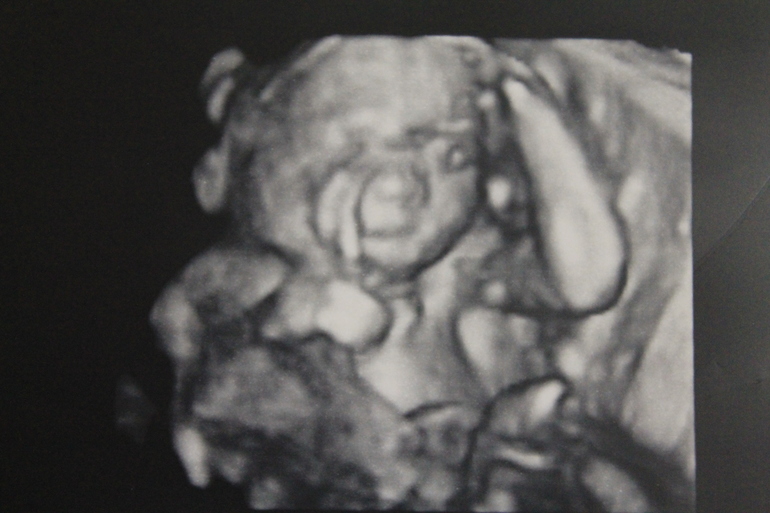

Результаты: УЗИ, КТГ, доплера, скринингаНам ровно 19 неделек... Сегодня были на скрининге

Делали 3D... Божечки, какая же она хорошенькая

Губки сказали у нас папины (как выразился врач... Анджелина Джоли отдыхает

)

Тьфу-тьфу-тьфу всё у нас хорошо, развивается на отлично, уже на неделю опережает)))) Весит 292гр.

Ну и конечно же фото